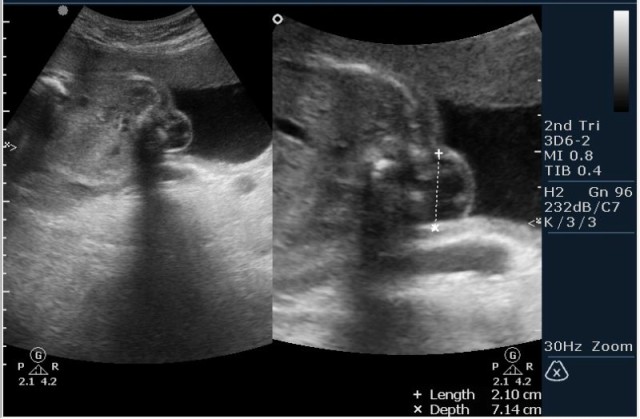

Женщина 23 года; из глухой деревни. К врачу обращалась один раз, когда забеременела. Дату последних месячных не помнит. Gravida 2, para 0. Направлена гинекологом для определения точного срока беременности и состояния плода.

1.Вентрикуломегалия/гидроцефалия (на сонограмме №1 размер задних рогов боковых желудочков 16мм при норме до 10 мм включительно;

На сонограммах головы плода визуализаируется гифдроцефалия, патогенетически связанная со спинномозговой грыжей (менингомиелоцеле) представленная в 2D и 3D режимах. В режиме Skeleton не удалось получить "картинку презентационного качества", плод начал сильно вертется; но рекоммендация очень грамотная :idea: , спасибо за ваш пост!